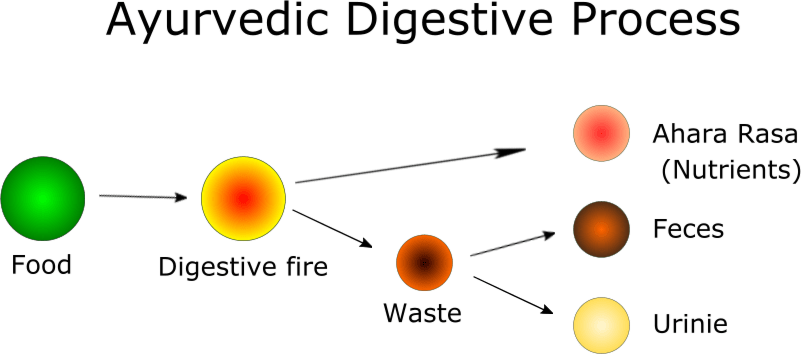

The food we take undergoes various digestion stages starting from the digestive fire (jataragni to the five elemental fire (panchamahabutagni).

The first step in digestion is that the food is digested by digestive fire (jataragni), which produces nutrient portions called Ahara rasa, and the waste products such as feces and urine (mala and mutra).